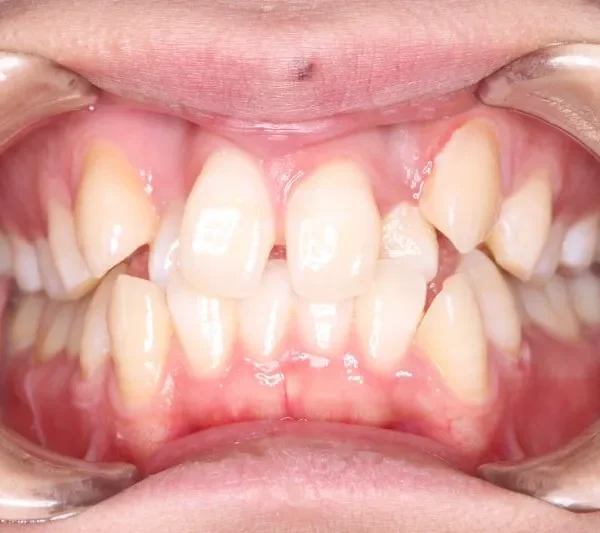

• 治療終了後

治療終了後

治療回数42回、3年1ヶ月の治療期間で矯正治療を終了しました。

主訴が改善され、ご満足頂きました。

正中のすき間については保定期間にも調整しています。